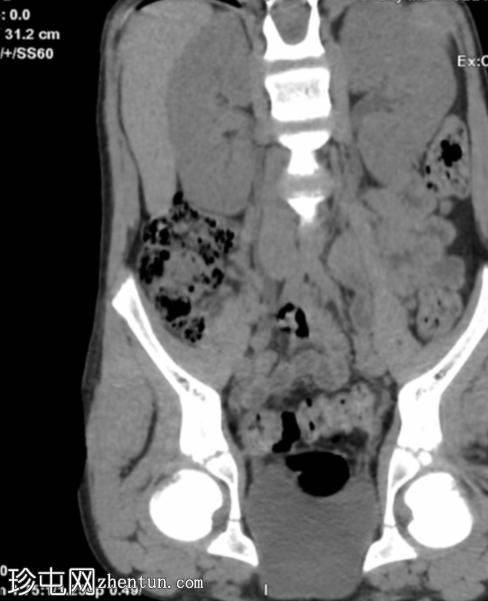

右侧腰痛。怀疑肾结石/输尿管结石。

年龄:10岁

性别:男

平扫

冠状位重建

显示输尿管显影

腹部和盆腔CT扫描结果正常。

泌尿系统正常。未见尿路结石或反流压改变。

本病例显示一名10岁男孩的腹部、盆腔和泌尿系统CT扫描结果正常。